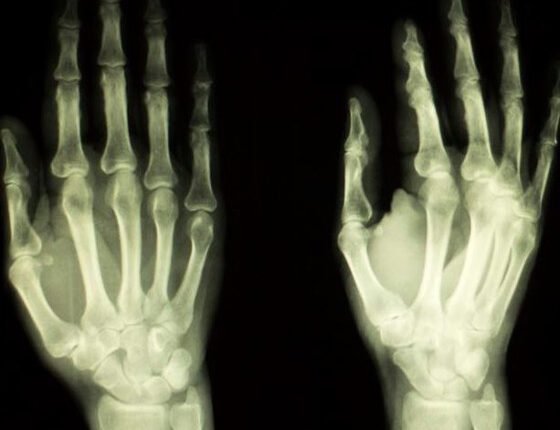

Κάθε δάχτυλο του χεριού έχει τρεις αρμούς. Εάν αυτοί οι αρμοί διογκωθούν, μπορεί να προκαλέσουν δυσφορία. Αυτό το πρήξιμο δεν είναι τίποτα άλλο από μια φλεγμονή των περιβαλλόντων ιστών.

Η διόγκωση των αρθρώσεων στα δάχτυλα του χεριού μπορεί να προέρχεται από διάφορες αιτίες. Ολες οι αρθρώσεις των δακτύλων είναι επικαλυμμένες με μια κολλώδη μεμβράνη που ονομάζεται αρθρικός υμένας, περιλαμβάνει αρθρικό υγρό και ο ρόλος της είναι να ευθυγραμμίζει την άρθρωση, έτσι ώστε αυτή να μπορεί να λειτουργήσει σωστά. Στην περίπτωση της ρευματοειδούς αρθρίτιδας, το αρθρικό υγρό μπορεί να διογκωθεί. Αυτό αναγκάζει το αίμα να συρρεύσει στην άρθρωση, προκειμένου να θεραπεύσει τη φλεγμονή, με αποτέλεσμα αυτή (η άρθρωση) να γίνεται ζεστή και να πρήζεται. Μια άλλη αιτία μπορεί να είναι η υπερπαραγωγή αρθρικού υγρού, το οποίο καλύπτει και προστατεύει την άρθρωση προκαλώντας φλεγμονή.

Η ρευματοειδής αρθρίτιδα μπορεί να είναι μία αιτία της διόγκωσης, η οποία οφείλεται σε ένα εξασθενημένο ανοσοποιητικό σύστημα που μεταφέρεται γενετικά, χωρίς ωστόσο αυτό να σημαίνει πως όποιος έχει το συγκεκριμένο γονίδιο θα αποκτήσει και ρευματοειδή αρθρίτιδα. Αν και ο καθένας μπορεί να βιώσει ρευματοειδή αρθρίτιδα, είναι πιο συνηθισμένη στους ενήλικες και ξεκινάει από τη νεαρή έως τη μέση ηλικία, με τις γυναίκες να υποφέρουν περισσότερο από τους άνδρες σε αναλογία τρία προς ένα. Ενας άλλος τύπος αρθρίτιδας, που ονομάζεται οστεοαρθρίτιδα, σχετίζεται περισσότερο με την ηλικία, αλλά μπορεί επίσης να προκληθεί από τραυματισμό της άρθρωσης.